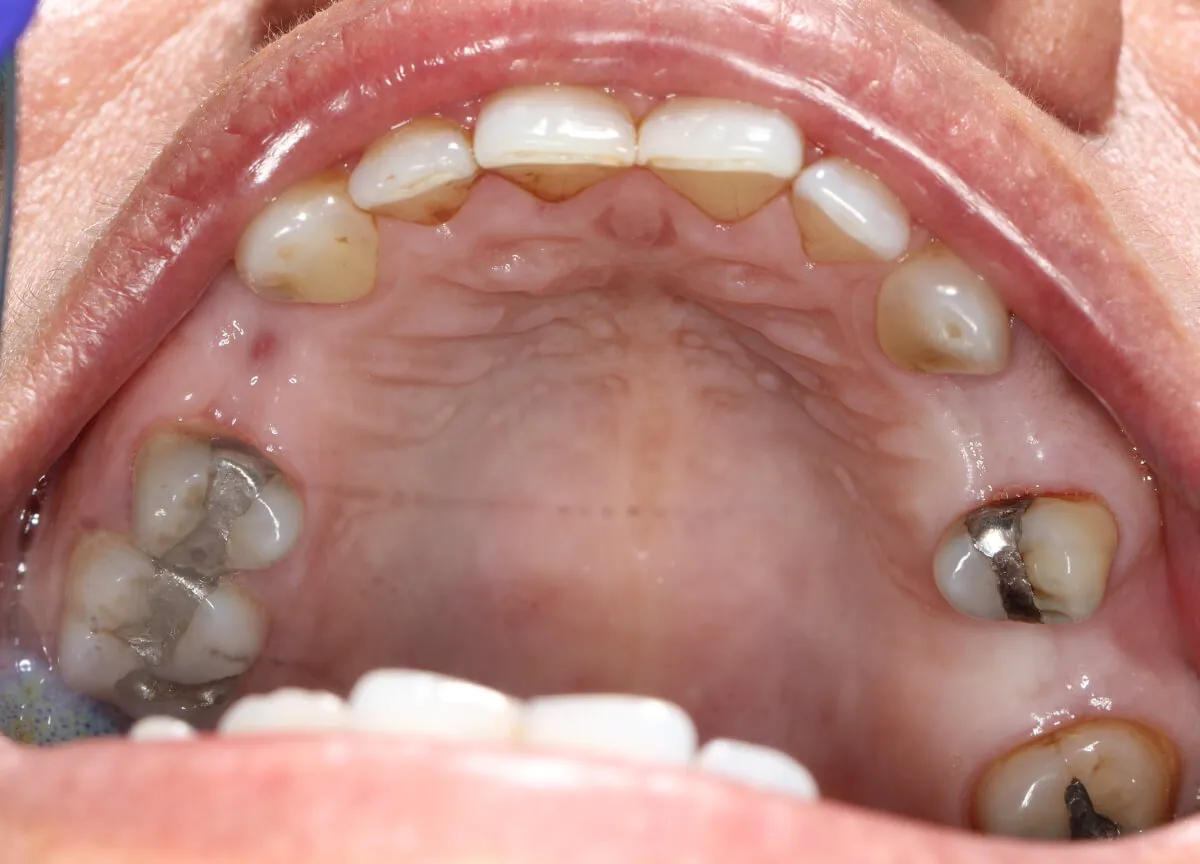

This lady received two dental implants and a bridge to replace her upper missing teeth. We restored her teeth, smile and boosted her confidence. She is very happy with the results and smiles with higher confidence.